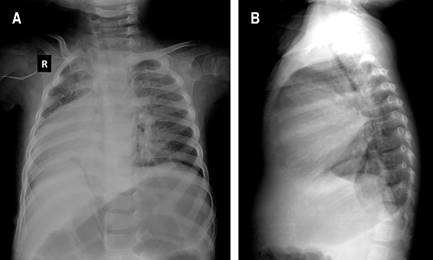

A los dos meses de edad, cardiología pediátrica mediante estudios de imagen estableció que presentaba dextrocardia y persistencia de conducto arterioso (Figura 1). En cuanto a su desarrollo se determinó retraso psicomotor grave, ya que a los dos años empezó la emisión de sonidos guturales y a sonreír a los tres. En tomografía de cráneo no se detectaron malformaciones del sistema nervioso central. Sin embargo, poco tiempo después aparecieron crisis convulsivas parciales complejas que fueron controladas con clonazepam; inicialmente eran dos crisis por semana, pero fueron disminuyendo a una por mes. En electroencefalograma se reportaron cambios epilépticos difusos. Por oftalmoscopía se evidenciaron cambios atróficos en ambos nervios ópticos; mientras que en potenciales evocados de tallo cerebral se identificó sordera moderada en oído derecho.

Figura 1: A) La radiografía de tórax anteroposterior evidencia el vértice cardiaco orientado hacia la derecha del tórax (dextrocardia) en el paciente con trisomía 13 completa. B) Radiografía lateral de tórax.

Un defecto que destacar, que estuvo presente en nuestro caso, pero es poco frecuente, es la dextrocardia, la cual se ha descrito previamente en dos publicaciones.20,21 Uno de ellos corresponde a la paciente con mayor tiempo de supervivencia reportada, una mujer afroamericana de 32 años, mientras el otro también es una mujer de 19 años. Señalamos que se han descrito diferentes defectos cardiacos congénitos, en más de 70% de los pacientes.5,13,22,23